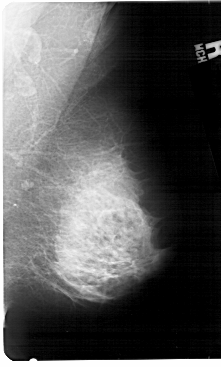

A_1396_1.LEFT_CC

LEFT_CC LINES 5026 PIXELS_PER_LINE 2941 BITS_PER_PIXEL 12 RESOLUTION 43.5 OVERLAY